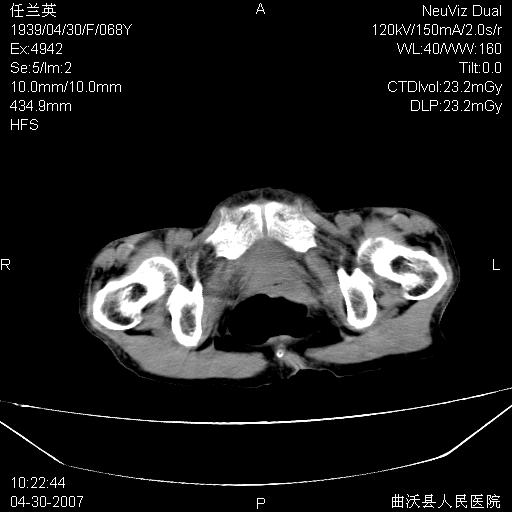

患者,女,68岁,感觉腹部憋涨发硬数天,查b超发现左盆腔有囊性肿物和少量腹水,行ct检查

1.考虑卵巢肿瘤并腹腔广泛性转移可能性大;

2.腹盆腔少量积液。

支持左侧卵巢恶性肿瘤伴网膜、腹膜广泛转移。

难的一见 典型 - 网膜饼  冰冻骨盆 可以当教学片了